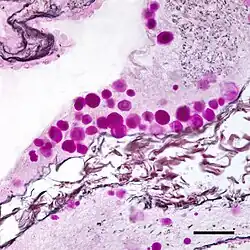

Corpora amylacea (CA) (from the Latin meaning "starch-like bodies") is a general term for small hyaline masses found in the prostate gland,[1] nervous system,[2] lung,[1] and sometimes in other organs of the body.[3] Corpora amylacea increase in number and size with advancing age,[3][4] although this increase varies from person to person.[3] In the nervous system, they are particularly abundant in certain neurodegenerative diseases.[2] While their significance is largely unknown, some researchers have suggested that corpora amylacea play a role in the clearance of debris.[1][3]

The composition and appearance of corpora amylacea can differ in different organs.[3] In the prostate gland, where they are also known as prostatic concretions, corpora amylacea are rich in aggregated protein that has many of the features of amyloid, whereas those in the central nervous system are generally smaller and do not contain amyloid.[3] Corpora amylacea in the central nervous system occur in the foot processes of astrocytes, and they are usually present beneath the pia mater, in the tissues surrounding the ventricles, and around blood vessels.[2] They have been proposed to be part of a family of polyglucosan diseases, in which polymers of glucose collect to form abnormal structures known as polyglucosan bodies.[3] Polyglucosan bodies bearing at least partial resemblance to human corpora amylacea have been observed in various nonhuman species.[3]